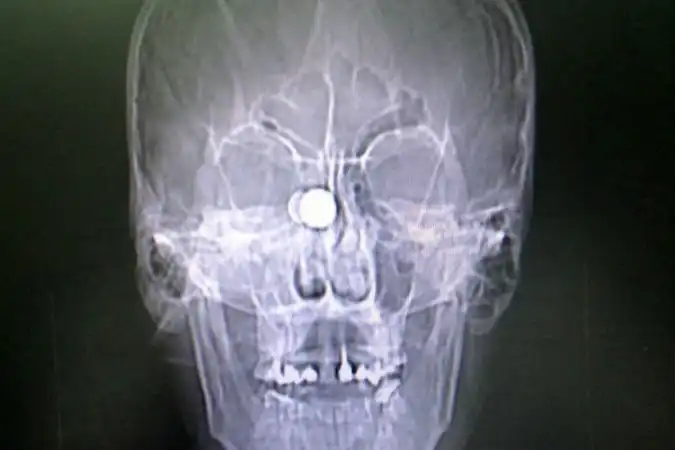

Про пациента Краевой клинической больницы, которого привезли накануне с пулей в голове (в прямом смысле слова), можно смело говорить – заново родился. Сам-то он ничего не помнит, только момент выстрела из травматического оружия. И прямо в глаз…Мужчина может считать этот день вторым рождением.

Сначала раненного доставили в глазной центр, где врачи удалили глазное яблоко. Потом перевели в краевую больницу. Отолорингологи краевой больницы провели, по сути, уникальную операцию высокотехнологичную операцию, чтобы извлечь из головы пациента пулю размером с орех. Самое опасное, что она находилась прямо в миллиметре от мозга молодого мужчины.

- Инородный предмет врачи ювелирно удалили под микроскопом, с применением эндоскопа через носовое отверстие, — рассказали в пресс-службе Краевой клинической больницы. — В настоящее время состояние пациента не вызывает у врачей опасений за его жизнь.